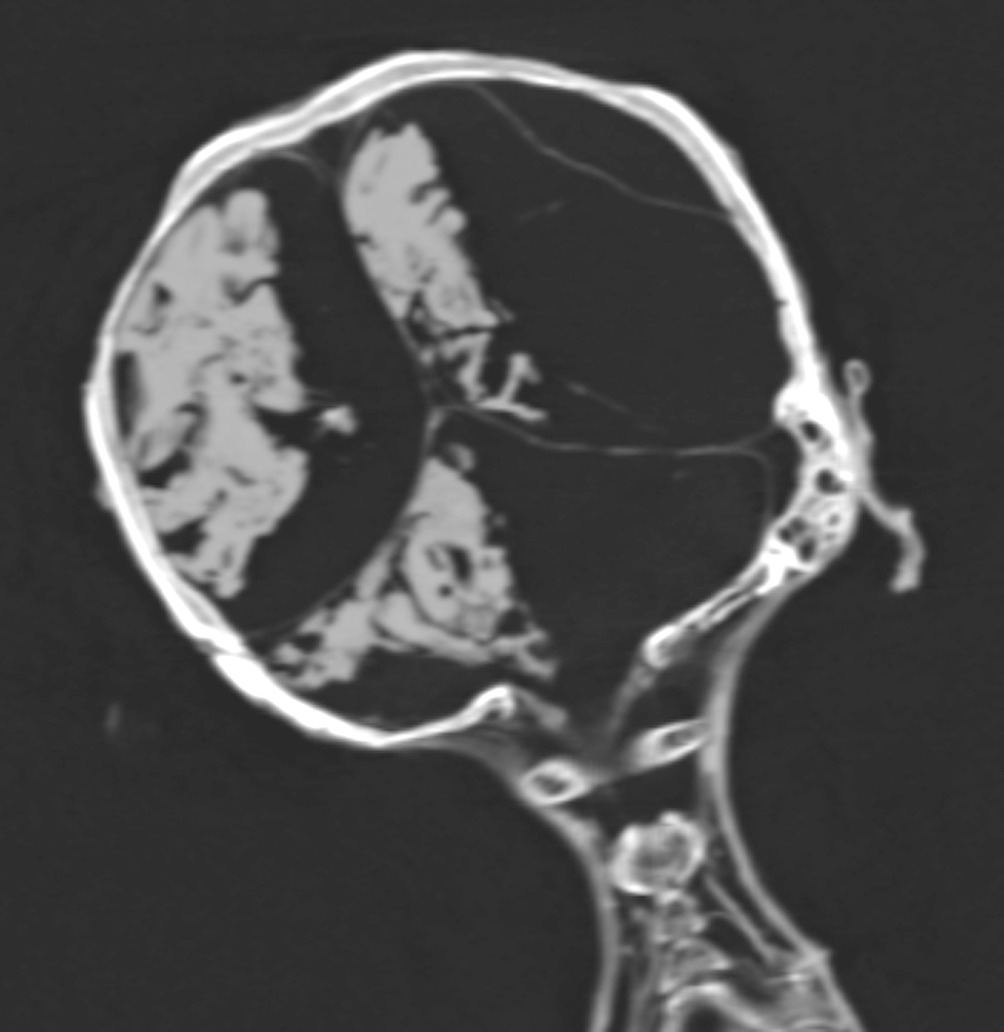

وتشير نتائج تصوير الأشعة المقطعية CT scan التى أجراها الدكتور زاهى حواس والدكتورة سحر سليم إلى أن مومياء المرأة الصارخة هى لسيدة ماتت فى العقد السادس من العمر وأن جثمانها (و على العكس من بنتاؤر Pentawere) نال عناية بالغة من المحنطًين الذين أزالوا الأحشاء ووضعوا مواد باهظة الثمن مثل الراتنج والحنوط المعطرة فى تجويف الجسم و استخدموا الكتان الطاهر فى لف المومياء .

وتشير نتائج التصوير المقطعى إلى أن “مومياء المرأة غير المعروفة”، “كانت مصابة بمرض تصلب الشرايين شديد الدرجة والذى أصاب العديد من شرايين الجسد، ومرض تصلب الشرايين هو مرض تنكسى يصيب جدار الشرايين بشكل تدريجى ما يؤدى إلى ضيق فى تجويف الوعاء الدموى وانسداده، ويتم تحديد أماكن تصلب الشرايين فى فحص الأشعة المقطعية كمناطق عالية التكلس داخل جدران الشرايين والتى يمكن التعرف عليها حسب مكان الشريان.

فأثبت فحص الأشعة المقطعية لـ “مومياء المرأة غير المعروفة” أنها عانت من تصلب فى شرايين القلب التاجية الأيمن والأيسر وكذلك شرايين الرقبة وشريان الأبهر البطنى والحرقفى وكذلك شرايين الطرفين السفليين والساقين.

و تفترض هذه الدراسة أن الأميرة ماتت فجأة بنوبة قلبية وهى على وضع الجسد الحالى ساقاها مثنية وملتفة عند الكاحل، وتسبب الموت فى ميل الرأس إلى الجانب الأيمن وارتخاء عضلات الفك مما أدى إلى فتح الفم، و تشير الدلائل أن المتوفاه ظلت لفترة كافية لعدة ساعات على هذه الوضعية قبل أن يتم اكتشاف الجثمان فأدى التشنج الذى يعقب الموت إلى تيبس العضلات والمفاصل وإبقاء مومياء الأميرة على وضعية الوفاة هذه فلم يتمكن المحنطون من تأمين إغلاق الفم أو وضع الجسد فى حالة الاستلقاء كما كان المعتاد مع باقى المومياوات، فيبدو أنه لم يهمل المحنطون عملهم عن عمد و لكن ظروف الوفاة أدت لوضعية المومياء هذه والغير معتادة، وأظهرت صور فحص الأشعة المقطعية أن المحنطون لم يستخرجوا مخ المومياء، حيث لا يزال يرى المخ بداخل تجويف الجمجمة ولكنه يميل إلى الجانب الأيمن وذلك لوضعية الجسد على هذا الجانب عند الموت و بعد التحنيط.

و ترجح هذه الدراسة من خلال ملاحظة خصائص طريقة تحنيط “مومياء المرأة الصارخة” مثل عدم استخراج المخ أنها قد تكون ميريت آمون ابنة الملك سقنن رع من نهاية الأسرة السابعة عشر 1558- 1553 قبل الميلاد و ليست ابنة الملك رمسيس الثانى (1279-1213 قبل الميلاد) من الأسرة التاسعة عشر.